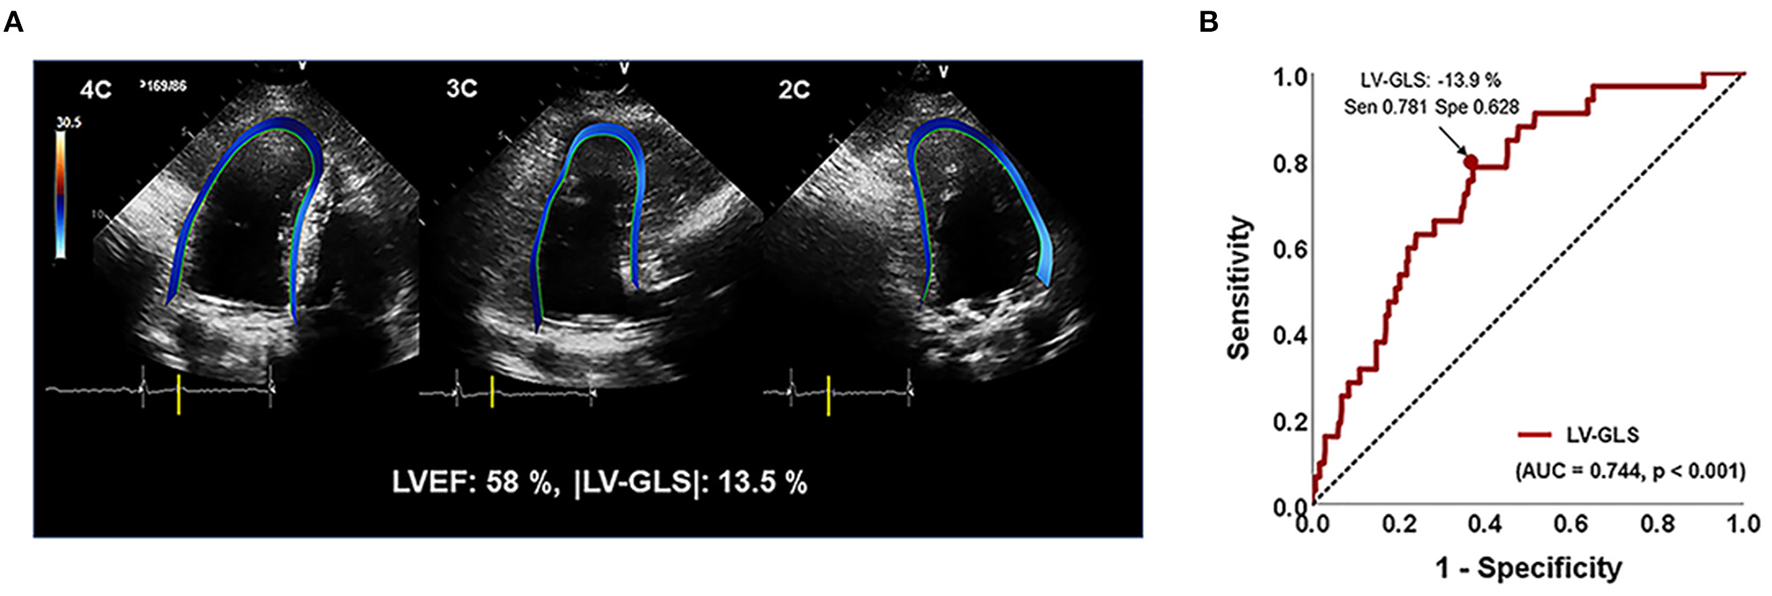

From two-dimensional images of the apical two-, three-, and four-chamber views, LV-GLS was measured offline using a vendor-independent software package (TomTec software; Image Arena 4.6, Munich, Germany), as described previously (14). For myocardial deformation analysis, the endocardial border was traced on the end-systolic frame in each selected image. The end-systolic frame was defined by the QRS complex or based on the smallest LV volume during the cardiac cycle. The software automatically tracked speckles along the endocardial border and myocardium throughout the cardiac cycle. The value for LV-GLS was obtained by averaging all segmental strain values from three apical views (Figure 1A). LV-GLS was analyzed for a single cardiac cycle in patients with sinus rhythm. In patients with AF, we selected an index beat method for the measurement of LV-GLS, which has been validated for LV-GLS in a previous study (15). |LV-GLS| was defined as the absolute value of post-operative LV-GLS (removing the conventional negative value of GLS data). |LV-GLS|preop was used to represent absolute value of pre-operative LV-GLS. Echocardiographic data and strain values were analyzed by an experienced cardiologist blinded to clinical data. We randomly selected 20 patients from the study population and analyzed the intra- and inter-observer reproducibility of LV-GLS measurement by Bland–Altman analysis. The intra-class correlation coefficients for |LV-GLS| were 0.978 and 0.962 with regard to intra- and inter-observer variation, respectively. The Bland–Altman analysis showed the limits of agreement (LOA) across a broad range of GLS values; the bias for intra- and inter-observer measurements of LV-GLS were 0.46% (range: −1.02% to 1.03%, 95% LOA) and 0.45% (range: −1.25% to 1.05%), respectively.

Figure 1

(A) Representative images for assessing LV-GLS. (B) Area under the receiver-operating characteristics curve (area under the curve) of |LV-GLS|. |LV-GLS|, the absolute value of left ventricular longitudinal strain. The Arrow indicated that the position of the value of sensitivity and specificity of 78% and 63% when |LV-GLS| has largest AUC.

In ROC analysis, the |LV-GLS| value showing the largest area under the curve (AUC) for the association with adverse clinical outcomes was 13.9% (AUC 0.744, p < 0.001), with a sensitivity and specificity of 78 and 63%, respectively (Figure 1B). In the subgroups according to cardiac rhythm, when GLS 14% is set as a cut off value, the sensitivity and specificity of 74 and 51%, respectively in the patients with AF and the sensitivity and specificity of 80 and 78%, respectively in the patients with sinus rhythm. |LV-GLS| showed a largest AUC of predictive value for clinical events than conventional parameters (LAVI > 40 ml/m2, AUC = 0.604, p = 0.065; TR >2.8 m/s, AUC = 0.670, p = 0.003). After dividing patients into two groups based on the cut-off value, those with |LV-GLS| ≤14.0% had poorer outcomes than patients with |LV-GLS| >14.0% (log-rank p < 0.001; Figure 3A). When the subjects were classified into three groups according to |LV-GLS| and PASP, those with |LV-GLS| ≤14.0% and PASP ≥35 mmHg had significantly worse outcomes compared to those in the other groups (log-rank p < 0.001; Figure 3B). There was no significant correlation between |LV-GLS| value and post-operative echocardiography timing (r = 0.018, p = 0.742). In addition, if |LV-GLS| was lower than 14.0%, there were more clinical events irrespective of post-operative echocardiography timing (Supplementary Figure 2). Also, in subgroup analysis according to follow-up duration, patients with |LV-GLS| ≤14.0% consistently showed a worse prognosis (Supplementary Figure 3).